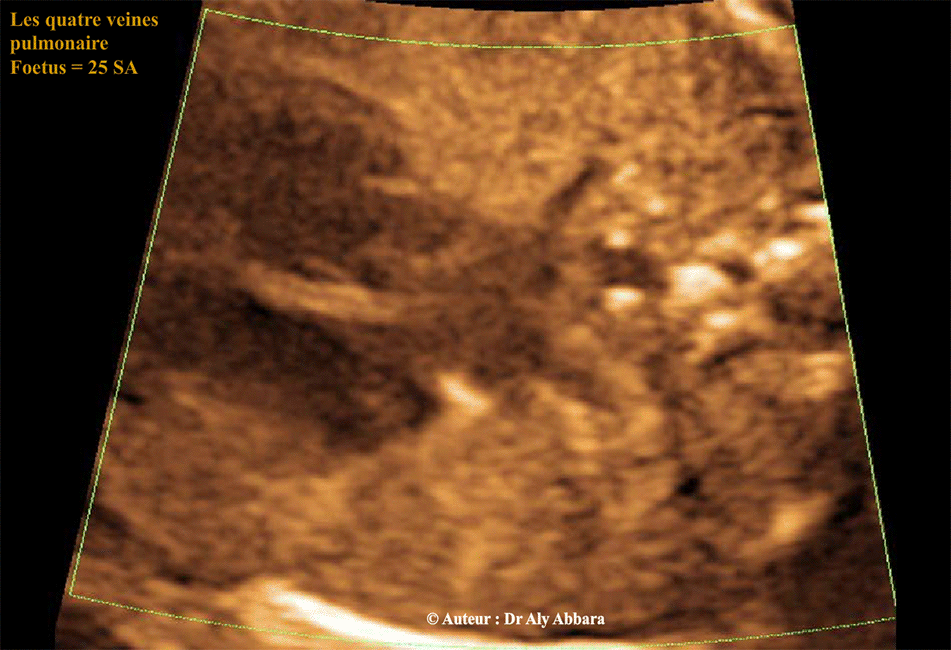

Les quatre veines pulmonaires (du retour veineux cardiaque) - Doppler énergie

Images échographiques montrant les quatre veines pulmonaires ; ce sont les vaisseaux du retour veineux pulmonaire (des deux poumons) vers l'oreillette gauche.